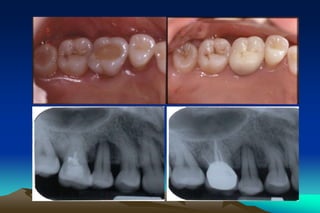

Detection skills

*Visual examination--- good light and a clean

field.

Compressed air supragingival calculus

chalky white; subgingival calculus dark

shadow

* Tactile sensation--- light exploratory strokes

are activated vertically up and down on root

surface

Detection skills *Visual examination---good light and a clean field. Compressed air supragingival calculus chalky white; subgingival calculus dark shadow * Tactile sensation--- light exploratory strokes are activated vertically up and down on root surface

• 40.

Detection skills * Tactilesensation--- the distance between apical edge of calculus and bottom of the pocket is 0.2 – 1.0 mm * Illumination